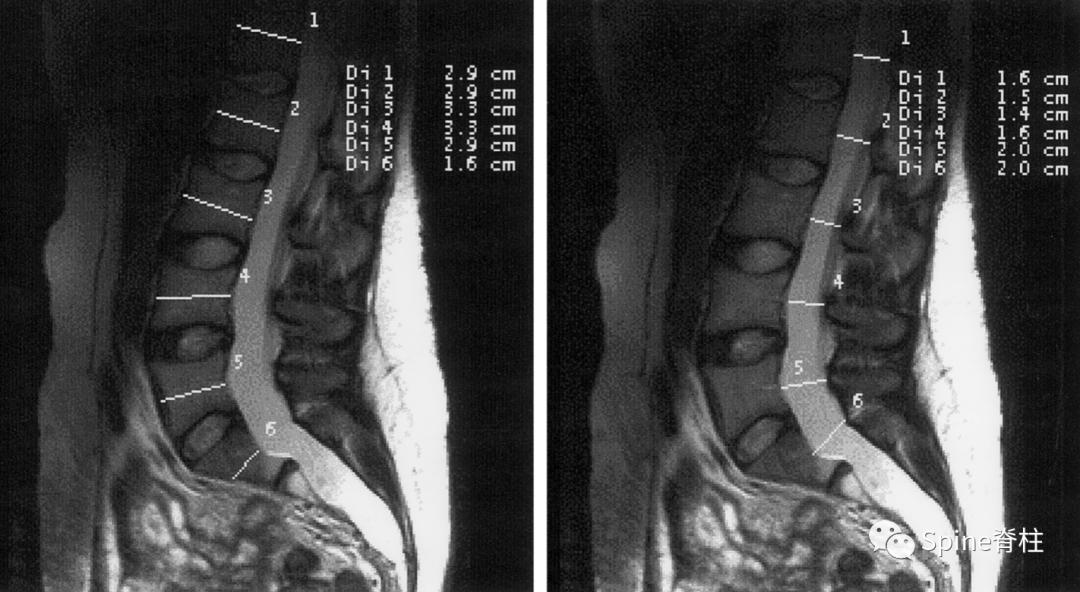

扇形缺损 (scalloping) 的测量。图a为马凡综合征伴硬膜扩张患者的CT正中矢状位重建。扇形缺损定义为椎体上下终板处宽度的平均值减去椎体中央处的宽度。对于这位患者来说,L5的扇形缺损值 (scalloping value) =[(d1+d3)/2]-d2=2.3mm;S1扇形缺损值=[(d4+d6)/2]-d5=4.2mm。图b是马凡综合征不伴硬膜扩张患者的CT正中矢状位重建。L5的扇形缺损值为1.6mm,S1扇形缺损值为0.4mm。

一位马凡综合征伴硬膜扩张患者的CT图像。a为正中矢状位重建,可见S2的椎管宽度大于L4。S1扇形缺损值为4.2mm。b为L5水平的横断面提示一个神经根袖的直接为6.6mm。因此,这个患者满足一个主要标准和两个次要标准。

一个马凡综合征伴硬膜扩张患者的MRI。a为T2正中矢状位提示S2硬膜囊的宽度大于L4,存在骶骨前硬膜膨出,S1的扇形缺损值为5.1。c为横断面提示一个神经根袖直径>7.0mm。因此,这个患者满足两个主要标准和两个次要标准。